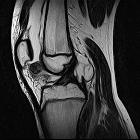

MRI

Features include

-

T1

- mass in the Hoffa fat pad

- generally low signal

- isointense to muscle

- some dark areas signifying calcification

- T2: high signal in the cartilaginous components

- PD: as above with T1, plus high intensity signal areas corresponding to medullary bone

- GRE: prominent signal voids within a nodular mass